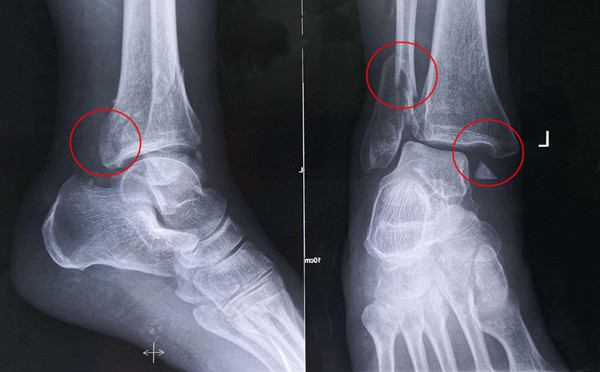

踝關節(jié)骨折在X影像上的表現(xiàn)有很多種。如內(nèi)踝骨折和外踝骨折,我們可以在影像上看到骨折處的骨折線是不連續(xù)的。還有后踝的骨折,內(nèi)踝、外踝、后踝聯(lián)合在一起發(fā)生的骨折,我們稱之為“三踝骨折”,這些都是在X影像上能夠顯示出來的。

內(nèi)踝骨折

后踝骨折